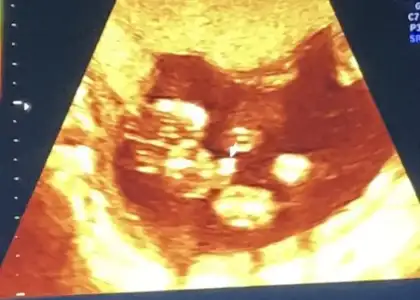

İlk iki foto alttan bakılandan son foto normal daha öncede atmıstım ama cok belli değil demiştiniz bu şekilde bi tahmin olabilirmi Ikra meyra Ikra meyra ☺️

Kızlar sizce cinsiyeti ne lütfen söyleyin sanırım ok'la gösterilen kısım genital bölge